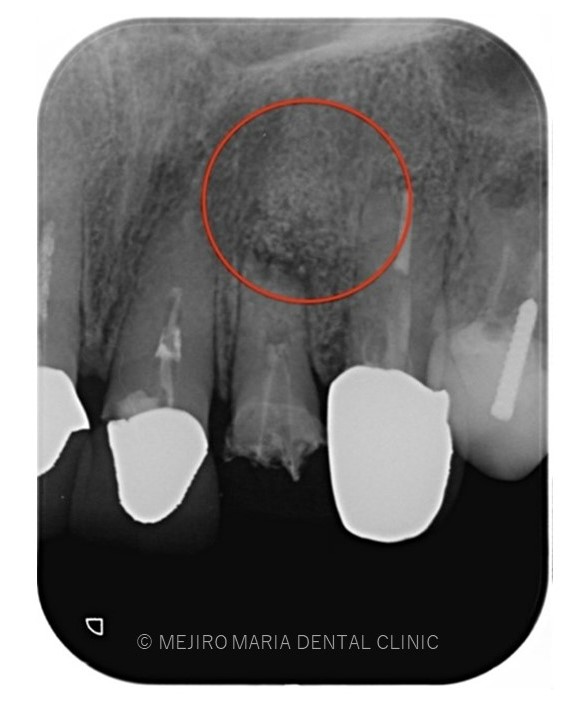

でのリカバリー_歯根端切除術直後のレントゲン画像.jpg)

でのリカバリー_術後3ヶ月後のレントゲン画像.jpg)

レントゲン写真より根尖部の骨は3ヶ月で順調に再生していると考えられます。

また、術前に訴えておられた違和感や腫脹、瘻孔は消失しており、現時点で経過は良好であると判断しています。

引き続き経過観察を継続していきます。